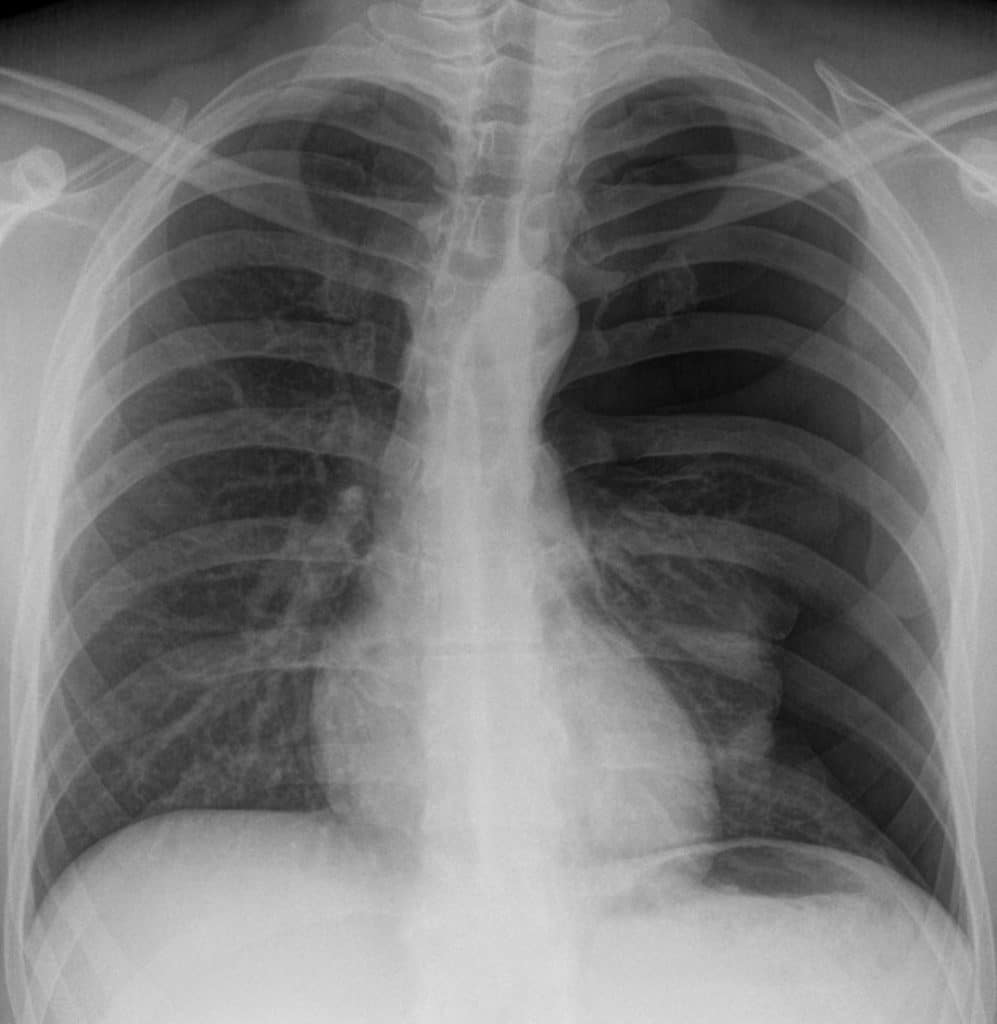

Fig 3

Radiographic appearance of a left pneumothorax.

Pneumothorax

A pneumothorax (commonly referred to a collapsed lung) occurs when air or gas is present within the pleural space. This removes the surface tension of the serous fluid present in the space, reducing lung extension.

Clinical features include chest pain, and shortness of breath, and asymmetrical chest expansion. Upon percussion, the affected side may be hyper-resonant (due to excess air within the chest).

There are two main classes of pneumothorax – spontaneous and traumatic.

• Spontaneous: A spontaneous pneumothorax occurs without a specific cause. It is sub-divided into primary (no underlying respiratory disease) and secondary (underlying respiratory disease present).

• Traumatic: A traumatic pneumothorax occurs as a result of blunt or penetrating chest trauma, such as a rib fracture (often seen in road traffic collisions).

Treatment depends on identifying the underlying cause. Primary pneumothoraces tend to be small and generally require minimal intervention, whereas secondary and traumatic pneumothoraces may require decompression to remove the extra air/gas in order for the lung to reinflate (this is achieved via the insertion of a chest drain).